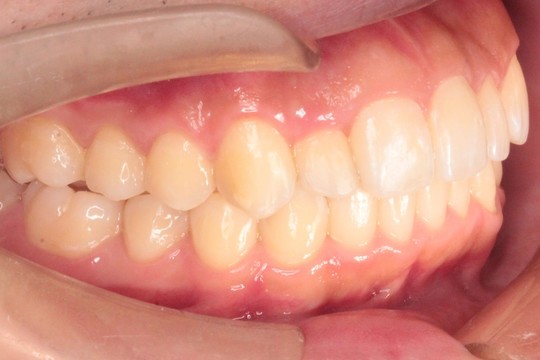

治療後

調布市の20代男性

主訴:歯並びをきれいにしたい

使用装置:インビザライン

治療期間:約3年

治療費用:93.5万円(税込)

治療結果:交叉咬合と叢生が改善されました